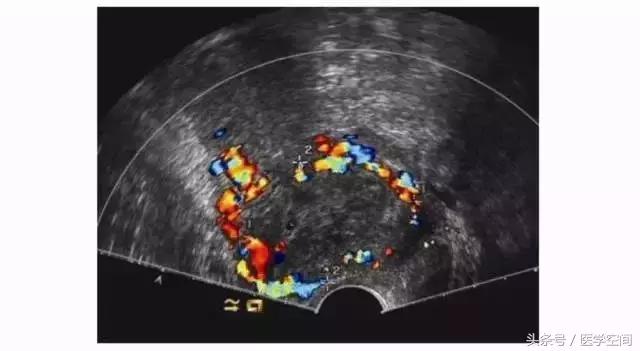

1.2不典型CSP的超声表现

又分为两种类型,第一种为宫腔内见孕囊型,孕囊多位于宫腔下段(较大孕囊可充满整个宫腔),但孕囊部分种植于剖宫产子宫瘢痕处,彩色多普勒超声(CDFI)检查瘢痕部位常可见较丰富血流信号(见图2);第二种为瘢痕部位包块型,子宫剖宫产瘢痕处未见孕囊,可见不均质低回声包块,其周边常可见较丰富血流信号(见图3)。不典型CSP容易漏诊及误诊。

图2不典型CSP的超声表现

图3不典型CSP的超声表现